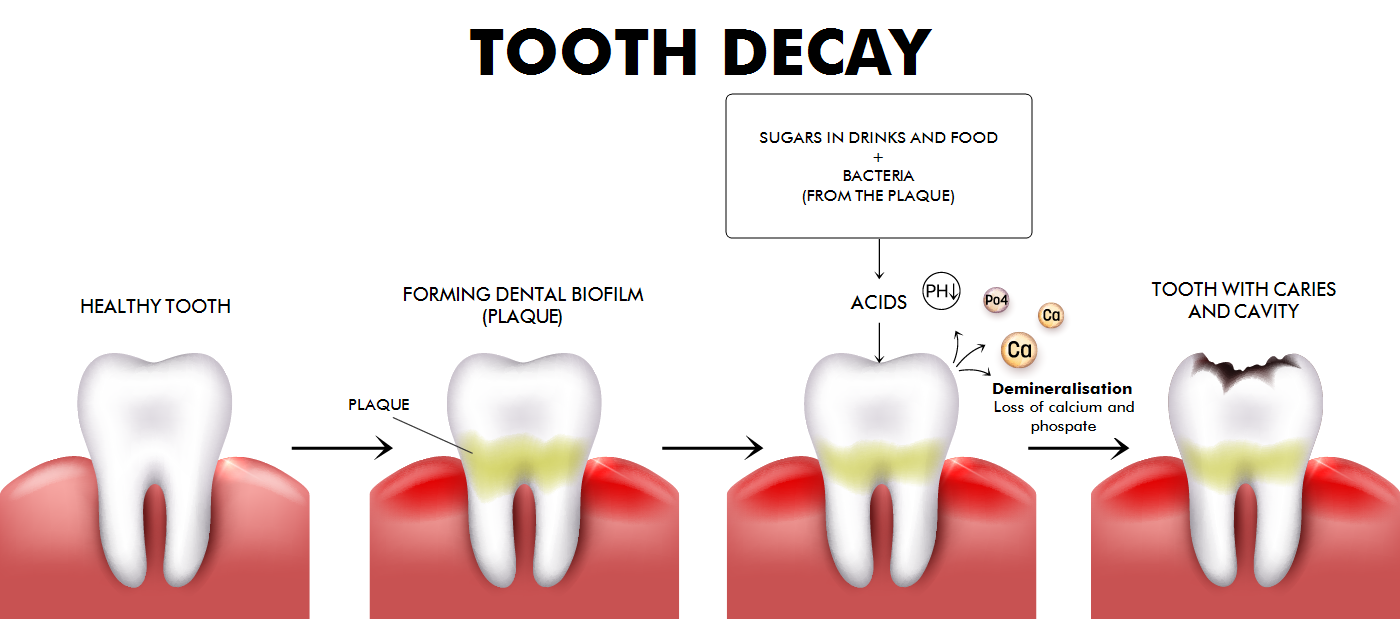

Tooth damage

Of course, there are many ways to damage one's teeth. Two of the most common reasons for tooth damage are periodontitis (inflammation of the gum) and caries (demineralization caused by acids emitted by bacteria). Here are two illustrations to visualize these processes:

The result are partially damaged teeth or loss of teeth.